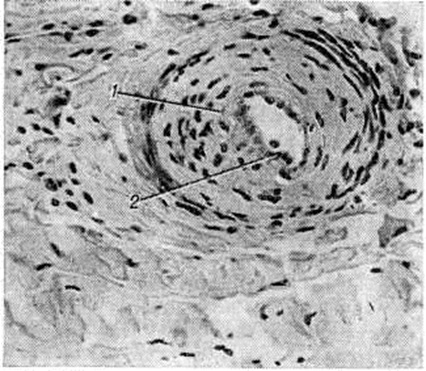

При активном течении патологический процесса васкулиты артериол и мелких артерий имеют пролиферативный характер с циркулярным разрастанием внутренней оболочки (рисунок 2). При электронной микроскопии в капиллярах поражённых тканей обнаруживается вакуолизация и деструкция эндотелия, а также многослойная базальная мембрана. По данным К луга (Н. Кlug) с соавторами (1977) и другие, при иммунофлюоресцентном исследовании материала, полученного при биопсии почек, мышц и кожи в стенках мелких артерий и капилляров, а также под сарколеммой мышечных волокон обнаружены депозиты IgM и комплемента.

Поражение кожи при системной Склеродермия часто сочетается с поражением суставов, костей и мышц. При поражении суставов обнаруживается экссудативно-пролиферативный синовит (смотри полный свод знаний) с фибринозными наложениями на поверхности синовиального слоя суставной капсулы, очаговой пролиферацией синовиоцитов, единичными продуктивными васкулитами, умеренно выраженным ангиоматозом, лимфоидно-макрофагальной инфильтрацией в субсиновиальном и фиброзном слоях. Суставной хрящ при системной Склеродермия теряет эластичность, становится ломким и быстро изнашивается; отмечается околосуставной остеопороз (смотри полный свод знаний). При отсутствии признаков артрита в суставной полости фактически отсутствует синовиальная жидкость, макроскопически синовиальный слой суставной капсулы становится плотным, лишённым ворсинок. При гистологический исследовании с трудом удаётся найти её органоспецифические особенности: синовиоциты на большем протяжении отсутствуют, синовиальный слой покрыт гиалиноподобными массами, субсиновиальный слой представлен бедной сосудами фиброзной соединительной тканью с обширными полями гиалиноза. При системной Склеродермия, сопровождающейся миопатическим синдромом, гистологический исследование скелетных мышц выявляет картину хронический миозита (смотри полный свод знаний) с разнокалиберностью мышечных волокон, гидропической дистрофией и миолизом части их, периваскулярными инфильтратами из лимфоцитов, макрофагов, полинуклеаров, васкулитами, разрастанием грануляционной и фиброзной соединительной ткани в эн дои перимизии. Более характерен фиброзирующий интерстициальный миозит (рисунок 3) с выраженным склерозом, липоматозом, гиалинозом эпи и перимизия, склерозом стенок сосудов, запустеванием капиллярного русла, мелкоочаговой периваскулярной лимфоидно-макрофагальной инфильтрацией, единичными васкулитами, очаговой перифасцикулярной или диффузной атрофией мышечных волокон.